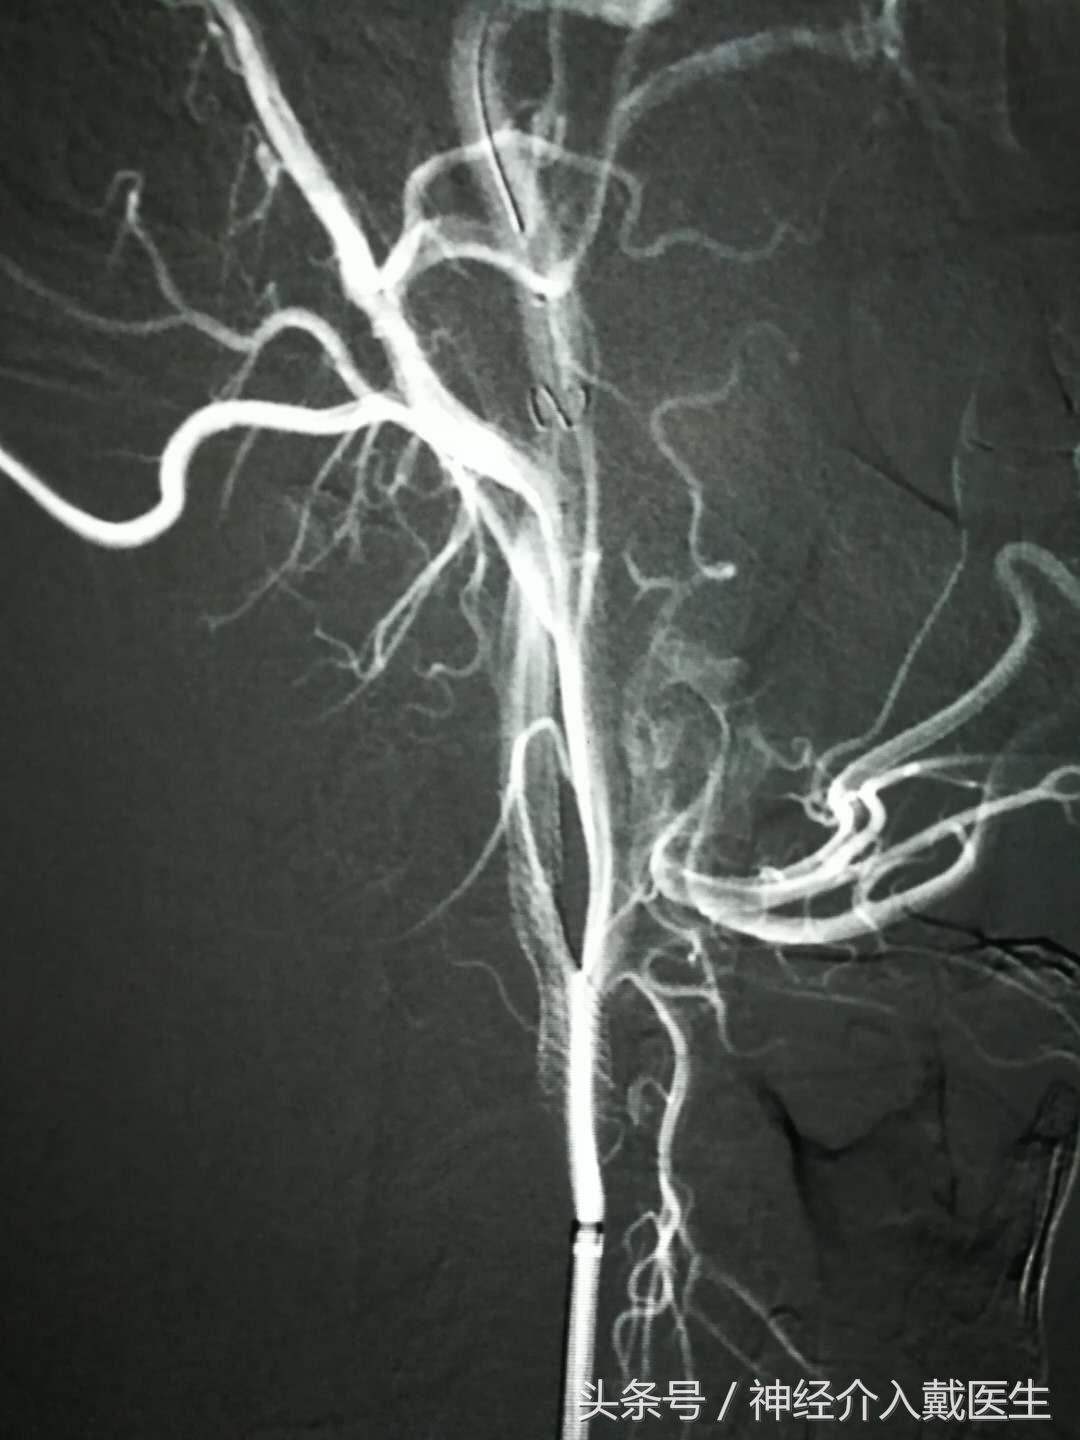

二,脑血管狭窄治疗,包括常见的颈动脉狭窄,和颅内血管狭窄。

支架手术的目的是为了维持狭窄的脑血管,原理上是通过一种细小的金属支架,撑开狭窄的血管,从而实现血管重新导通的目的,让血液能够顺畅通过不畅通的区域。支架手术的流程是这样的:首先利用纤细的导管,将金属支架带到血管堵塞的地方,然后通过支架置入使得原本堵塞的血管恢复畅通。手术造成的损伤非常小,安全度也比较高,所以在脑血管疾病方面得到了非常广泛的应用。手术过程是怎么样的呢?支架手术并不需要在头部“动刀子”,手术属于微创手术,整个过程可以分为以下三个步骤:首先,在股动脉处建立通路;然后,医生通过特殊传送系统,将气囊导管送到血管狭窄处,然后球囊膨胀,使支架扩张定型,使血管恢复通畅;最后,将已消气的气球从血管中取出,并将导管从血管中撤出,因为狭窄的虽然已经扩张,但是不维持,仍然容易狭窄,所以通过微导管放一个支架到狭窄的血管,整个手术就结束了。这个手术虽然不用开刀,但是到底安全吗?但在毕竟是在微小的脑血管里面进行的进行的,相信很多人不禁会疑惑,手术到底安不安全呢?脑血管支架置入手术,在国内外都是治疗脑血管疾病的常见方法之一,技术在国内外已经非常成熟。关于手术的其他事项从安全性以及效果来说,脑血管支架手术都是比较靠谱的治疗方法,